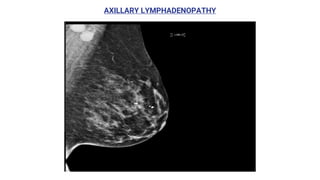

AXILLARY LYMPHADENOPATHY